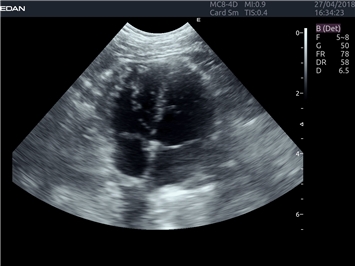

EDAN Acclarix LX4 VET представляет собой профессиональную ультразвуковую систему, специально разработанную для ветеринарных исследований. Сочетание стабильности, высокой производительности и эффективности делает эту систему идеальным выбором для современной ветеринарной практики.

Режимы акустической прозрачности 3D:

Да

Объемное сканирование:

M-режим:

B-режим, Двухмерное сканирование: